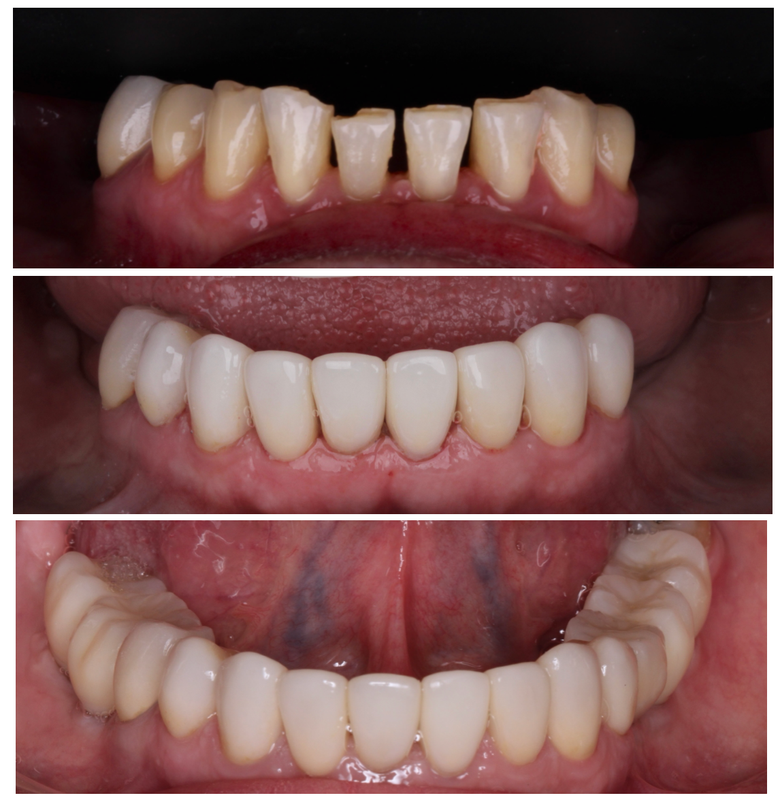

Prótesis fija

Coronas, puentes y rehabilitaciones completas.